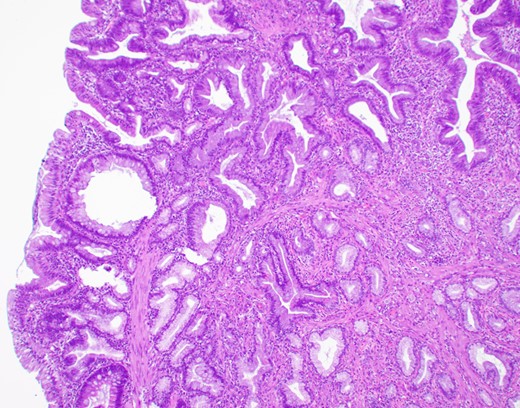

The patient is a 63-year-old Chinese male who presented with lethargy, 10-pound weight loss and painless jaundice for 1 week. Patient had a prior episode of jaundice of unclear etiology 2 years prior treated medically and had just emigrated from China 1 month prior to admission. Patient was febrile to 102.4°F, jaundiced with a total bilirubin of 18.5 mg/dL. Abdominal ultrasound showed intra and extrahepatic bile duct dilation, the distal CBD was dilated to 25 mm. Patient underwent endoscopic retrograde cholangiopancreatography (ERCP), which showed thick yellow mucus and no stones (Fig. 1). A sphincterotomy was performed and a pigtail stent placed. Computed tomography (CT), magnetic resonance imaging and magnetic resonance cholangiopancreaticogram failed to show a pancreatic head mass, distal CBD mass or stones causing obstruction (Fig. 2). Cold forceps biopsy of the papilla, endoscopic ultrasound with fine needle aspiration biopsy (FNAB) of pancreatic head, and CBD brushings were all nondiagnostic. CBD stents occluded two times in 2 weeks’ time secondary to thick mucus, requiring multiple ERCPs with stent exchanges (Fig. 3). After extensive multidisciplinary discussions regarding unclear etiology of distal CBD obstruction and extensive discussion with patient and family, the decision was made to perform a Whipple procedure for diagnosis and definitive treatment. Intraoperatively, choledochoscopy was performed, which showed very thick yellow mucus and frond-like mucosa near the ampulla. Final pathology showed a 2.0 × 1.5 × 0.5 cm3 granular lesion in the distal CBD. There was prominent biliary epithelial proliferation with tubular–papillary architecture and minimal nuclear atypia in association with chronic inflammation, stroma reaction and smooth muscle proliferation. The overall histological change in the distal CBD resembled that of AH seen in gallbladder, likely non-neoplastic change (Figs 4 and 5). At 1 year follow-up, he is doing well and his jaundice has resolved.

Microscopic appearance (H&E, ×20). Hyperplastic surface epithelium with myofibroblastic stromal proliferation.